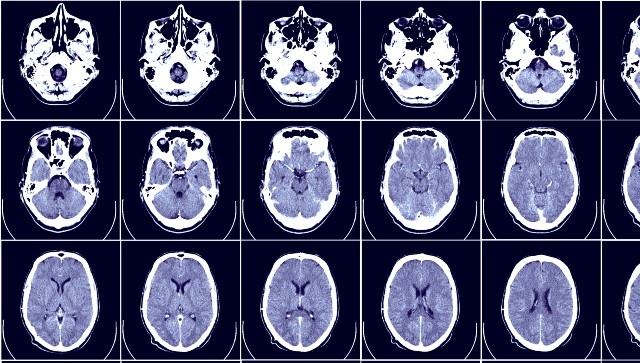

National Epilepsy Day is marked on 17 November annually to create awareness about the medical issue. The day is also used for making people aware of the symptoms and treatment of the disease. Epilepsy is a non-communicable disease in which recurrent seizures occur due to the brain generating sudden, abnormal bursts of electrical energy. Around 50 million people suffer from epilepsy globally according to the World Health Organization (WHO). Of the total number of people affected, about 80 percent live in developing countries, with over three-fourths of epilepsy patients not receiving adequate medical care in developing nations. In India, about 10 million suffer from epilepsy and the seizures associated with it. Why is epilepsy caused? The disease is caused due to a variety of factors such as brain infections, strokes and brain tumours, brain damage from prenatal and perinatal injury and congenital abnormalities. Epilepsy can also occur in any age group due to head injuries or a prolonged high fever during childhood. As the country marks National Epilepsy Day today, here’s a look at what the symptoms of the medical issue are and how you can manage them: Symptoms of Epilepsy: ― Loss of consciousness in the patient ― The feeling of stiffness in muscles of the face or the arms and legs. Some people may also experience a tingling sensation in their muscles ― Patients also experience sudden twitching or jerks in their arms and legs. If you are experiencing an epileptic seizure, you can try the following tips to manage them: ― Take the medications prescribed for seizures. ― Consult the doctor if the medicines are not effective. Do not discontinue your medication without consulting your doctor. ― Avoid drinking alcohol as it leads to seizures. If any person close to you is suffering from the disease, here is what you can do if they are suffering from a seizure: ― Do not panic or try to restrain the person suffering from a seizure. ― Remove any sharp or harmful objects from the vicinity of the person. ― Allow the patient to rest and put a pillow under their head. ― Be with the patient till medical help reaches. ― Roll the person gently to one side to ensure that any fluid in the mouth can come out safely.